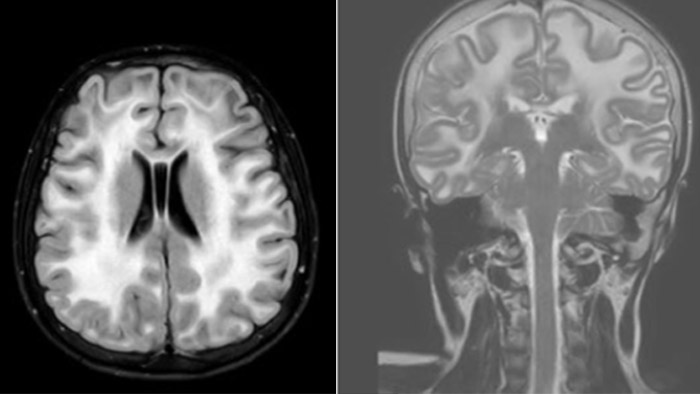

Hydrocephalus post hemorrhagic Both pictures show a ventriculoperitoneal shunt. With our previous scanner our hydrocephalus protocol needed about 25 min. With Ambition the examination time is about 14 min. including a CSF PCA sequence to show flow in the aqueduct.

Rostral meningitis and arachnoiditis Both images are from the same 3D T1-weighted post contrast sequence in a newborn, under treatment.